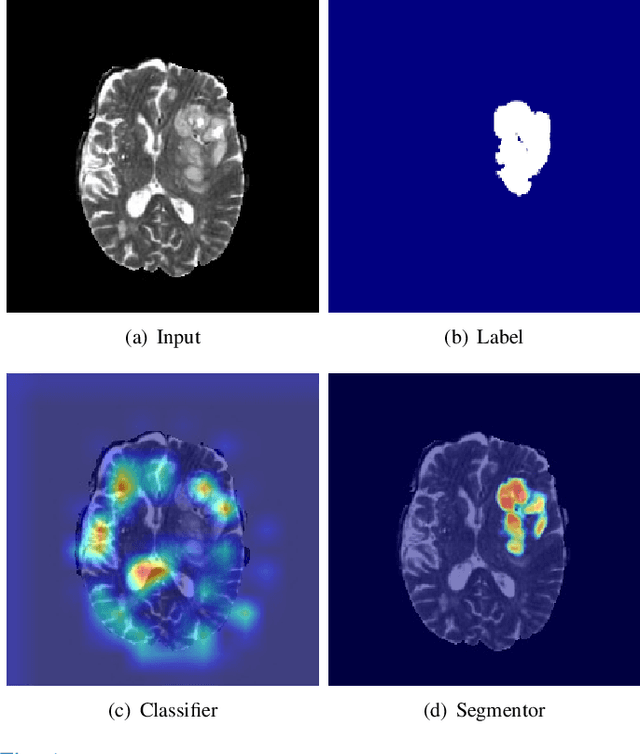

Synthesizing a subject-specific pathology-free image from a pathological image is valuable for algorithm development and clinical practice. In recent years, several approaches based on the Generative Adversarial Network (GAN) have achieved promising results in pseudo-healthy synthesis. However, the discriminator (i.e., a classifier) in the GAN cannot accurately identify lesions and further hampers from generating admirable pseudo-healthy images. To address this problem, we present a new type of discriminator, the segmentor, to accurately locate the lesions and improve the visual quality of pseudo-healthy images. Then, we apply the generated images into medical image enhancement and utilize the enhanced results to cope with the low contrast problem existing in medical image segmentation. Furthermore, a reliable metric is proposed by utilizing two attributes of label noise to measure the health of synthetic images. Comprehensive experiments on the T2 modality of BraTS demonstrate that the proposed method substantially outperforms the state-of-the-art methods. The method achieves better performance than the existing methods with only 30\% of the training data. The effectiveness of the proposed method is also demonstrated on the LiTS and the T1 modality of BraTS. The code and the pre-trained model of this study are publicly available at https://github.com/Au3C2/Generator-Versus-Segmentor.